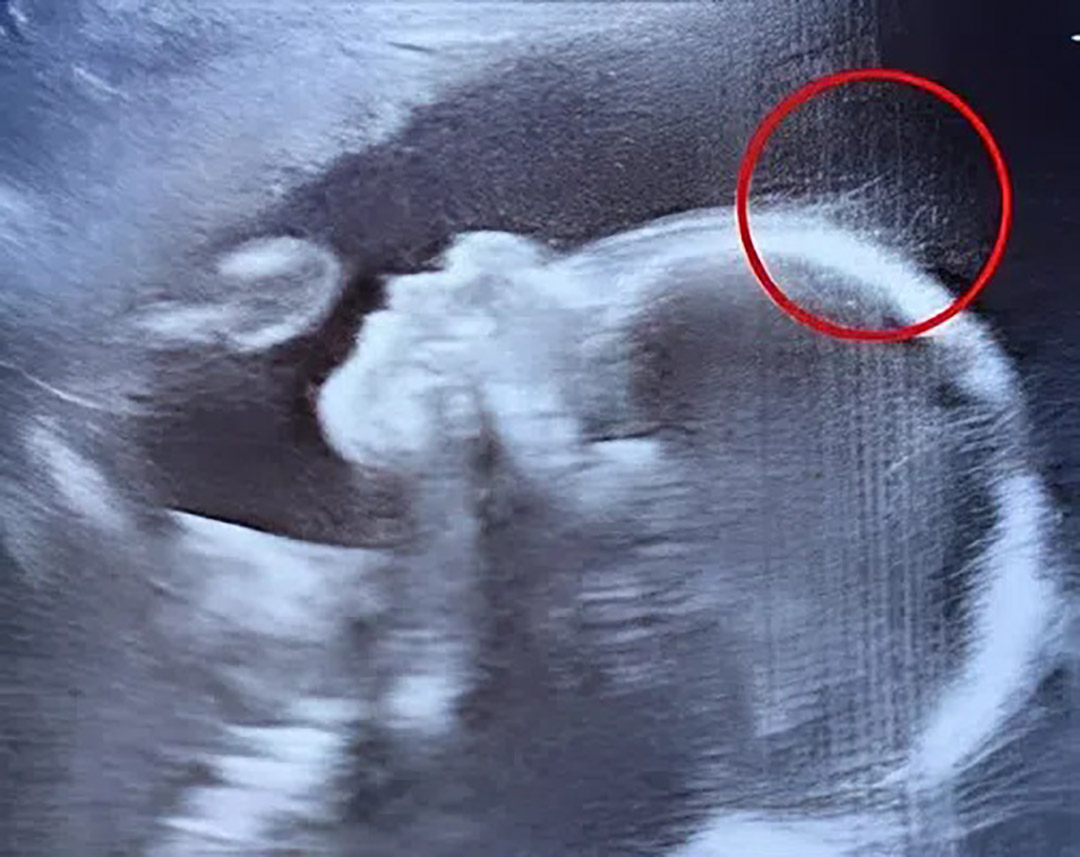

Lors d'une consultation prénatale de routine, une future mère constate avec émerveillement une caractéristique inhabituelle chez son bébé à naître. Cette singularité, d'abord perçue comme anecdotique, se révèle à l'accouchement être un spectacle rare et captivant.